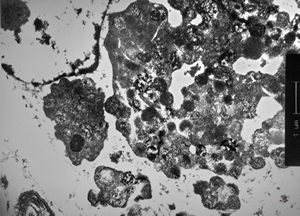

clotted blood - fibrin and granulocytes

F,44y. | striations of fibrin - heart atrium, myxoma

M,28y. | striations of fibrin - aortal valve, endocarditis